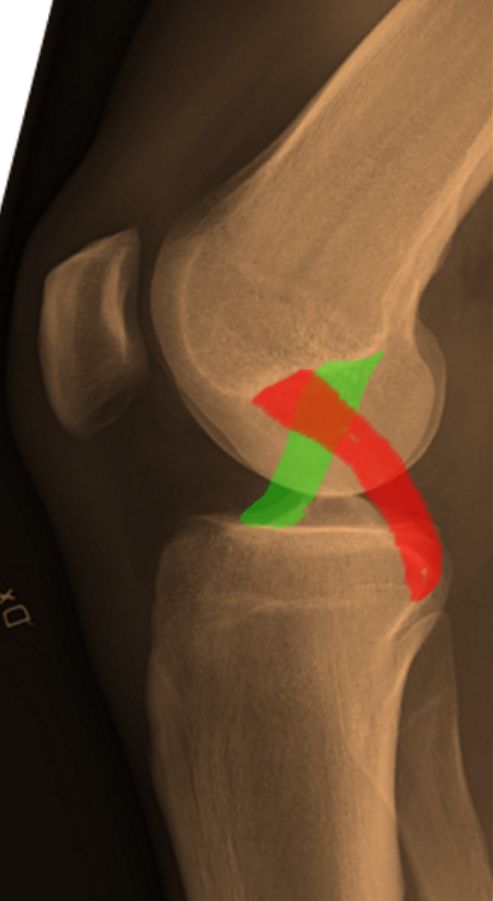

Join us as our hosts discuss the Cruciate Ligament Injuries chapter from Orthopaedia, available at www.orthopaedia.com/cruciate-lig...